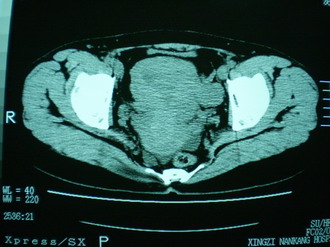

子宫增大,内可见类三角形低密度区,子宫后方可见类圆形团块状影,内部密度不均匀,可见靶样结构,结合病史考虑1子宫后方宫外孕(宫内假孕囊形成)2子宫肌瘤合并妊娠

子宫明显前倾,增大,宫颈增大呈分叶状。子宫直肠窝见不规则形水样低密度。(膀胱胀尿不理想)

考虑:1、宫颈部占位;

2、子宫直肠窝少量积液(盆腔炎所致)。

考虑:1、宫颈部占位(宫颈癌?);

2、子宫直肠窝少量积液。